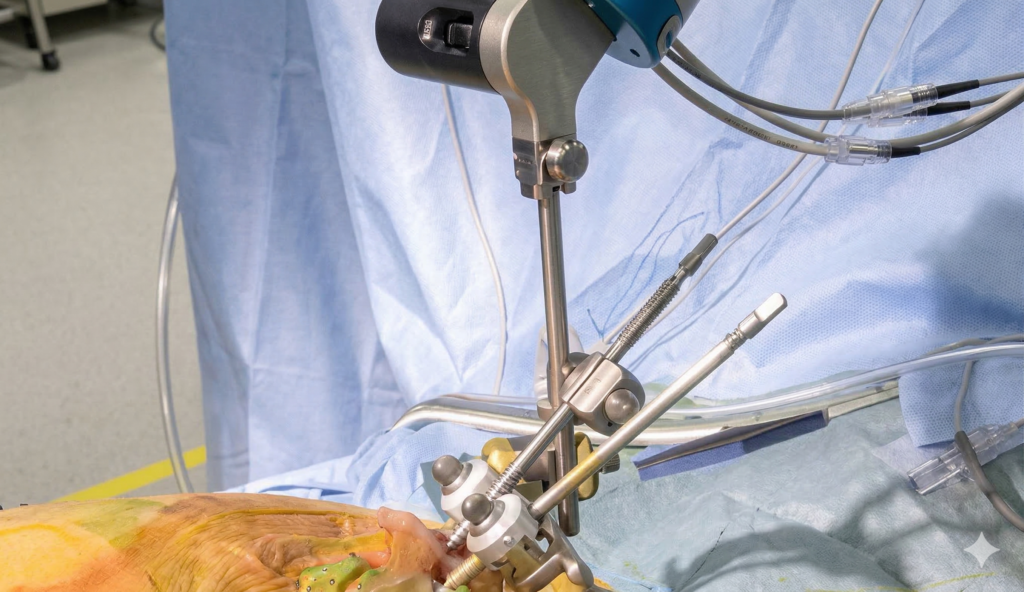

Dr. Kishore Kumar Panda is the first surgeon in Odisha to offer computer-navigated hip replacement. This advanced technology ensures highly accurate implant positioning, improved joint alignment, and long-lasting results.

Explore the care at the best orthopaedic clinic in Bhubaneswar, featuring clinic spaces, procedures, and patient care moments that reflect advanced facilities and compassionate treatment.